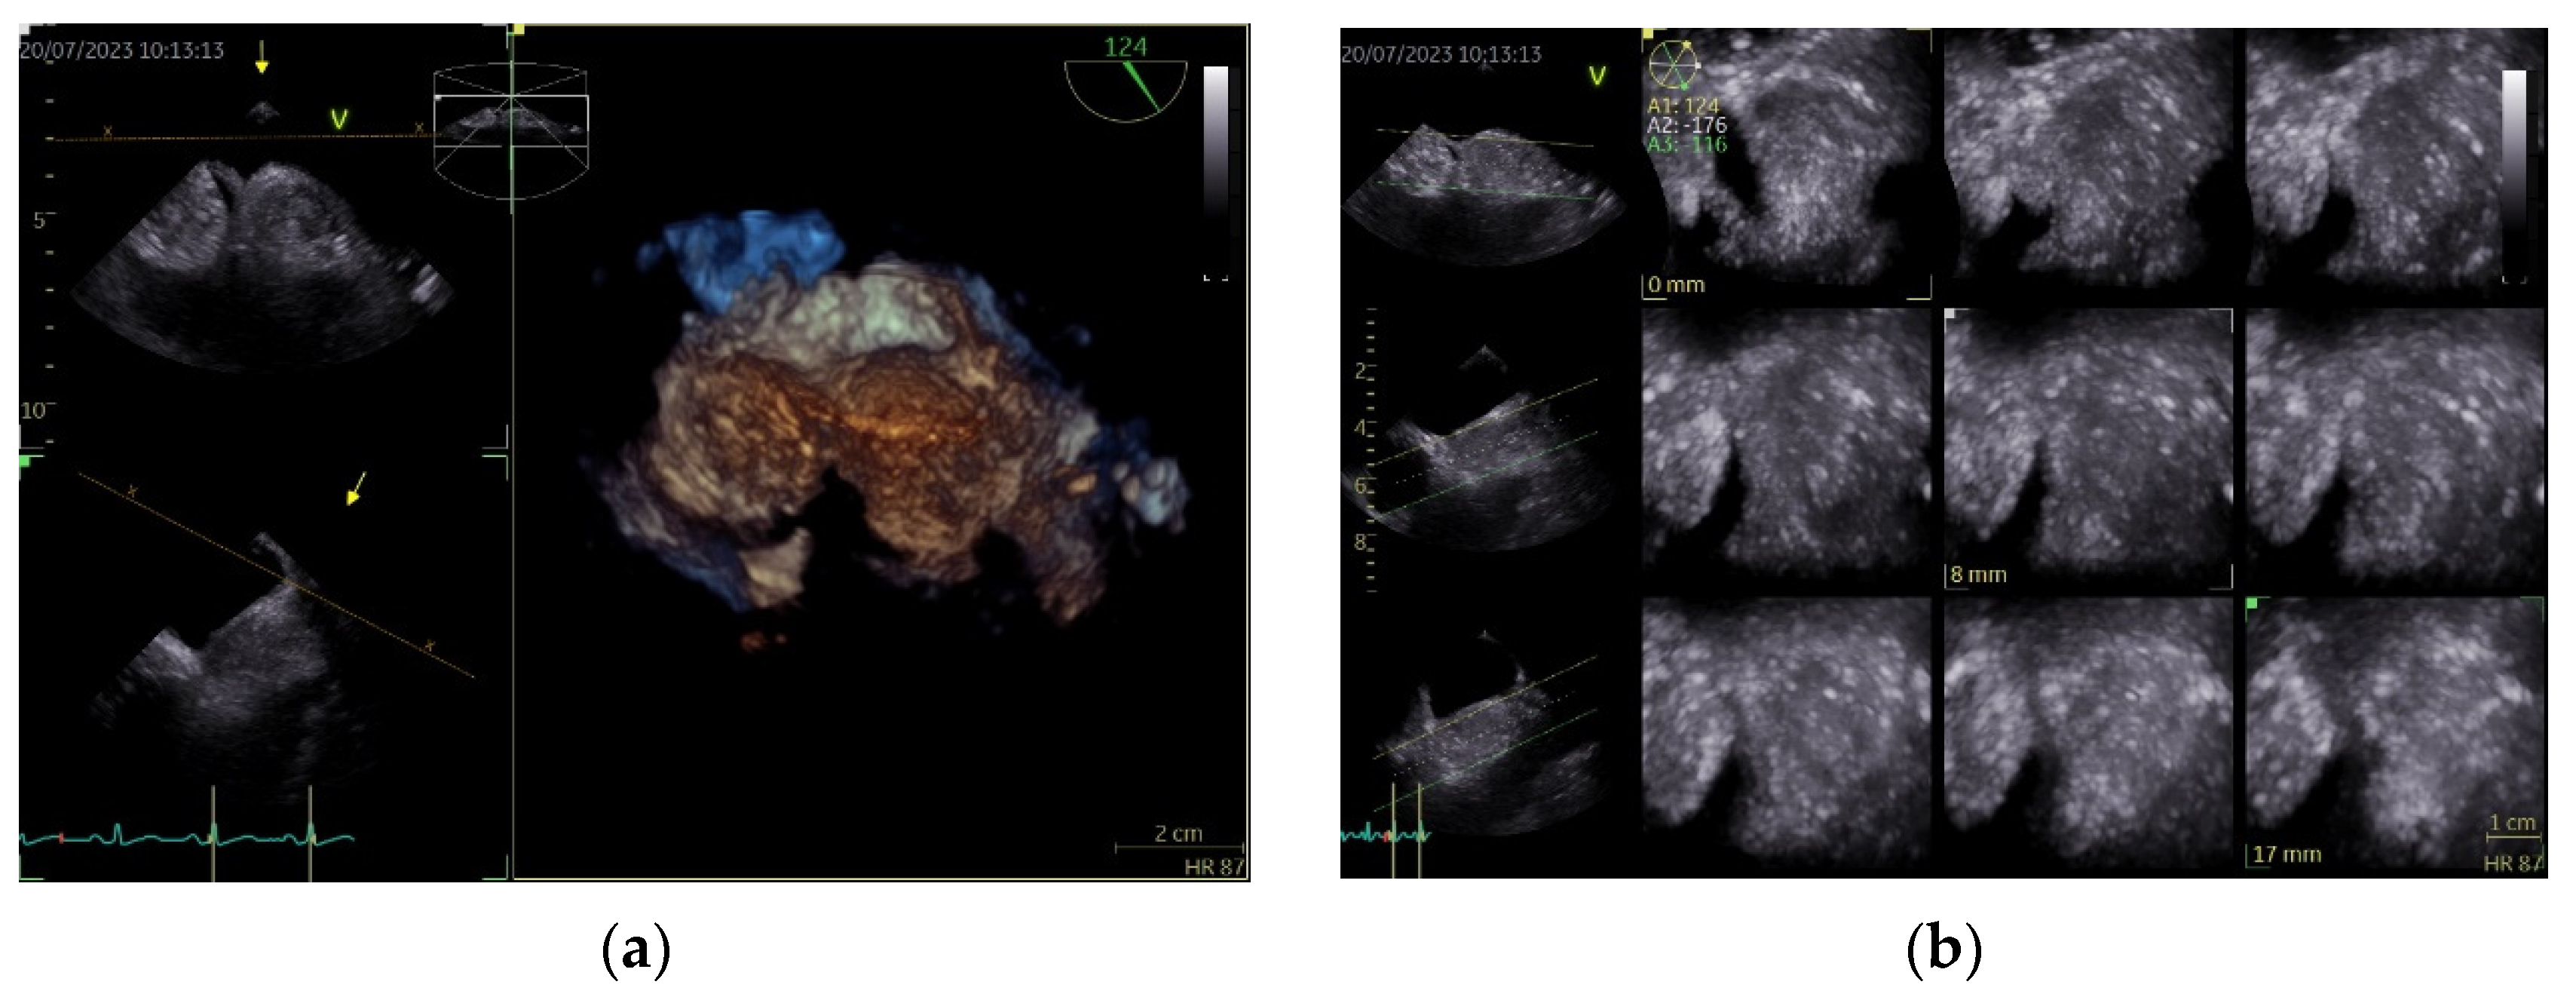

Figure 3.

Transesophageal echocardiography, tridimensional reconstruction. (a) Four-dimensional zoom acquisition revealing two so-called masses attached to the IAS with the appearance of distinct structures, bulging in the RA (inferior) and imprinting the LA surface of the IAS (superior); (b) 4D zoom acquisition after multislice analysis, confirming the homogenous aspect of the “structures”.

Tridimensional echocardiography evaluation of the IAS may bring supplemental information in case of an optimal image, especially during TOE, since it reveals a spatial and complete visualization of the IAS and the infiltrative nature of the pathology. On the other hand, in our case, with a quasi-suboptimal image even with TOE, it may not bring sufficient proof for a definite diagnosis. By creating multiple slices through the structure, it can provide data regarding composition but no clear information about the tissue type. The presence of hypertrophied myocytes and different types of adipocytes may create the appearance of a pseudo-capsule, which may raise some questions of differential diagnosis, as it did in our case.